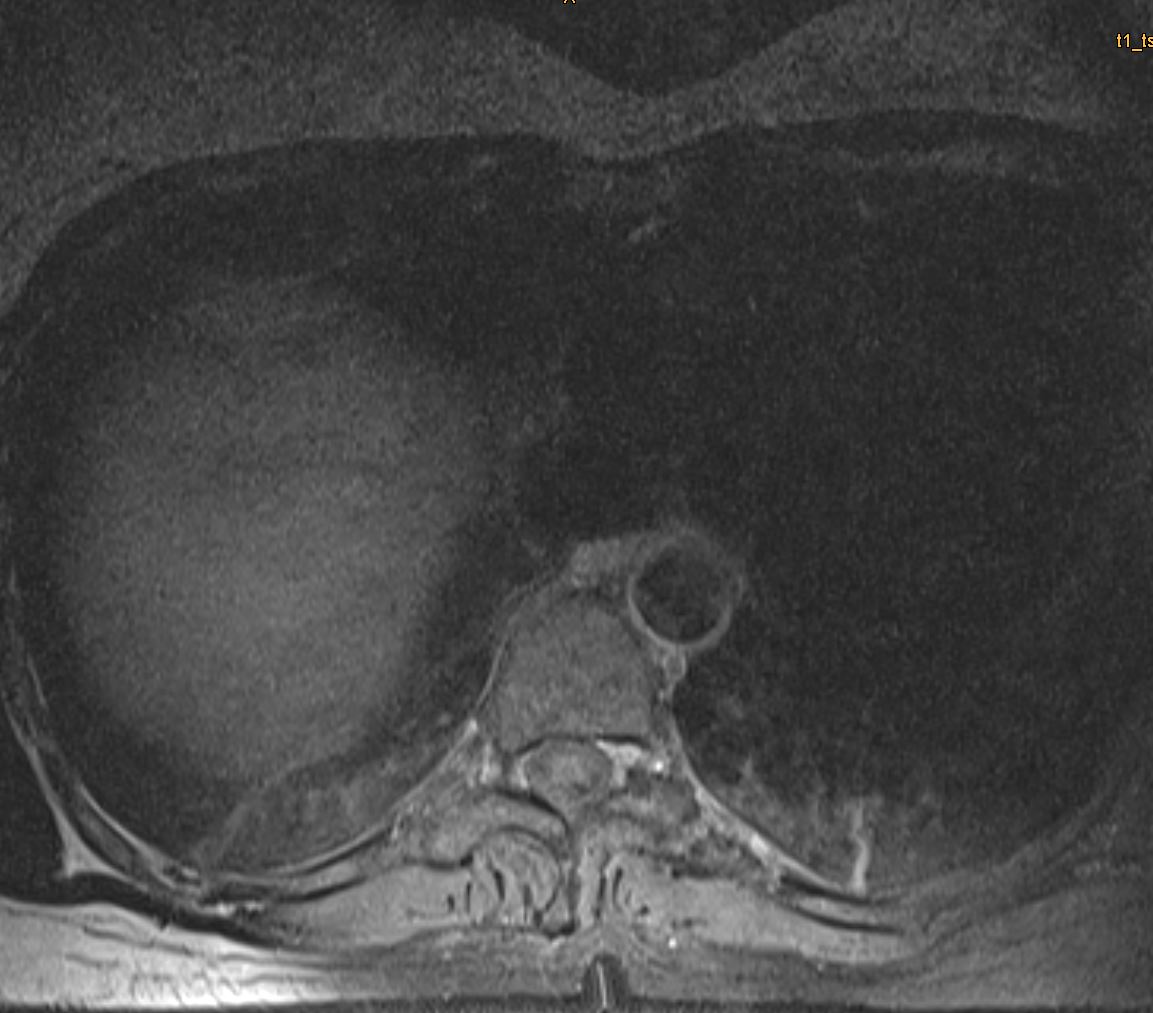

Θωρακικό Σβάννωμα Θ9/Θ10